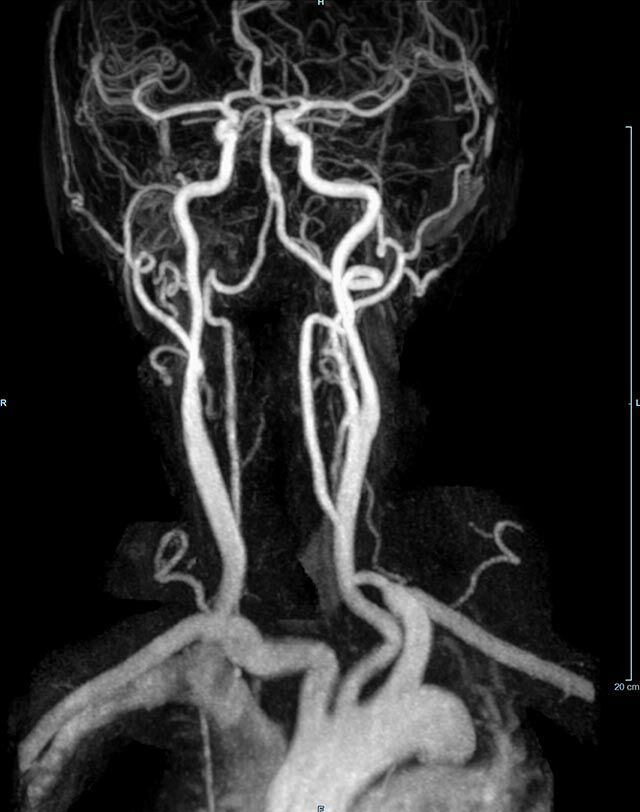

Halsgefäße

• Halsgefäße zur Therapieplanung (z.B. Stent, Operation)

MR-Angiografie (MRA)

Angiographie ohne Kontrastmittel

• MR-Angiografie ohne Kontrastmittel

• Time of Flight (TOF)-Angiographie

• Phasenkontrastangiographie (PCA). Geeignet zur Quantifizierung Stenose-/Insuffizienzgrad z.B. bei Herzklappen, falls echokardiographisch die Untersuchungsbedingungen eingeschränkt sind.

Je nach Fragestellung und Körperregion Gefäßdarstellung ohne Kontrastmittel bei Kontrastmittelunverträglichkeit oder terminaler Niereninsuffizienz möglich.

Ganzkörper Angiographie mit Kontrastmittel

• MR-Angiographie mit Kontrastmittel

• Erfassung arterieller und venöser Gefäße/Bypässe aller Körperregionen mit 3D-Rekonstruktion

• je nach klinischer Fragestellung zeitaufgelöste MR-Angiographie (4D-MRA) z.B. bei Frage arteriovenöse Fistel/ Shunt oder Darstellung Unterschenkelarterien vor geplanter Bypassoperation.